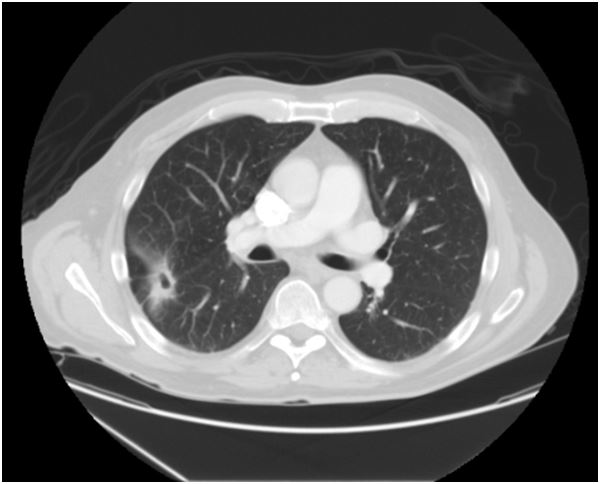

A chest CT scan was repeated this admission which revealed a 2 cm cavitary mass in the right mid lung with a thick wall and spiculations extending to the pleural surface.

Because of the concern for malignancy, a video-assisted thoracoscopic (VATS) wedge resection was performed. The resected nodule on gross inspection was found to be a 2.6 x 1.7 x 0.8 cm firm intraparenchymal nodule with a gray-tan solid cut surface and central 0.5 x 0.4 x 0.3 cm cavity space. Microscopic examination revealed intrabronchiolar aggreg ates of fibroblastic tissue and mononuclear cells invading alveolar spaces, as well as presence of multinucleated giant cells with no evidence of organisms on acid fast or Gie msa staining.